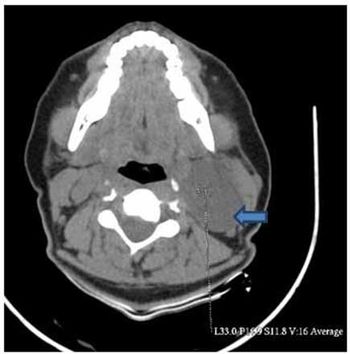

Case history: A 45-year-old female patient was referred to our hospital with painless swelling on left side of neck. She had been aware of the swelling for the last eight months which was gradually increasing in size